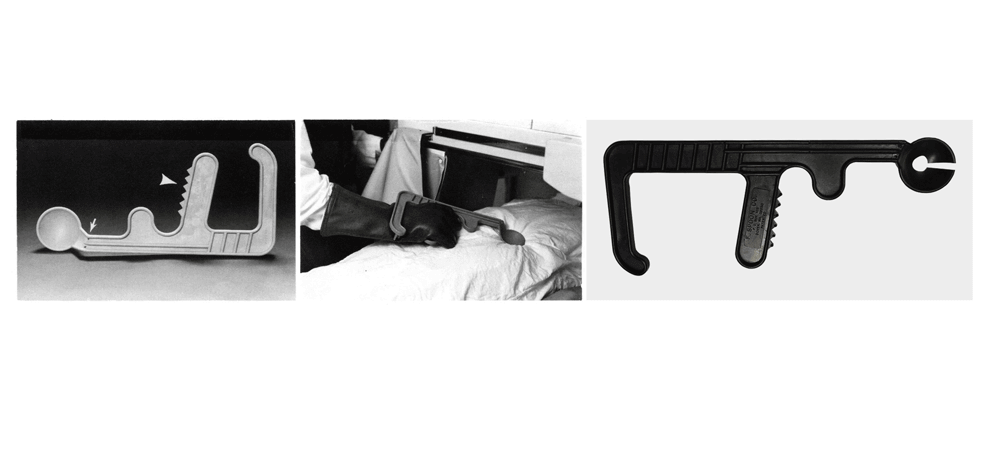

Compression Paddle

This compression paddle is a handheld external device used to facilitate CT fluoroscopy–guided percutaneous interventions in the abdomen. The device was designed using computer-aided design software starting from an existing gastrointestinal fluoroscopy compression device. 3D printing was used to physically prototype the device. The device facilitates access to interventional targets and its use minimizes radiation exposure of radiologists. The handgrip and curved armrest allow the operator

to control the device while applying continuous

pressure to the abdomen. The keyhole

cutout in the device was designed to help secure

two rubber bands that maintain a gap in the sterile

cover, facilitating placement of the spoon around a

needle while maintaining sterility.